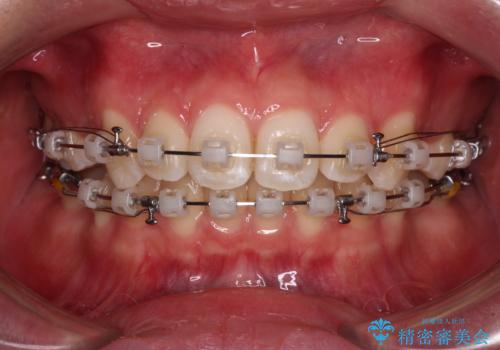

- 矯正装置

- クリアブラケット

- 上の前歯が下唇に引っかかる感じが気にして来院された患者様です。

上下歯列の前後位置を見ると、上顎が全体的に前方に位置しており、上顎前歯が前方に突出しているものの、横顔の印象はそれほど口元が突出しているものではない状態でした。

口元を極端に引っ込めた印象にしないため、上顎は左右第一小臼歯2本を、下顎は左右第二小臼歯2本を抜歯し、ワイヤー装置にて矯正治療を行うこととしました。